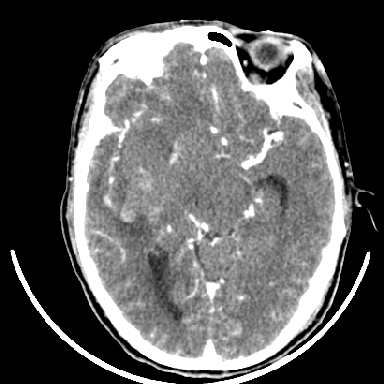

标题: CT6056:脑出血(血管畸形?)

m 40突发头痛左侧偏瘫3小时

考虑高血压性脑出血,依据:

1是高血压性脑出血的好发部位,形态呈肾形,是高血压性脑出血的常见形状

2增强时占位效应加重了,考虑出血还没有停止

3病灶周围水肿不是太厉害,一般肿瘤出血水肿多非常明显

4病灶周围的‘软组织’影没有明显的强化

5至于脑血管畸形引起的出血,暂时没有看到明显的畸形血管影,也不太支持

支持右侧基底节脑出血

右侧基底节区脑出血.

支持右侧基底节区(主要为外囊区)原发性脑出血。

另附部分资料:“血液溢出血管外形成血肿,其内含有大量血红蛋白、血浆白蛋白,球蛋白,因这些蛋白对x线的吸收系数高于脑质,故ct呈现高密度阴影,ct值达40~90h,最初高密度灶呈非均匀一致性,中心密度更高,新鲜出血灶边缘不清。基底节区血肿多为“肾”型,内侧凹陷,外侧膨隆,因外侧裂阻力较小,故向外凸,其它部位血肿多呈尖圆形或不规则形”

术中抽出40ml陈旧血液,血肿底部似见一条索血管影